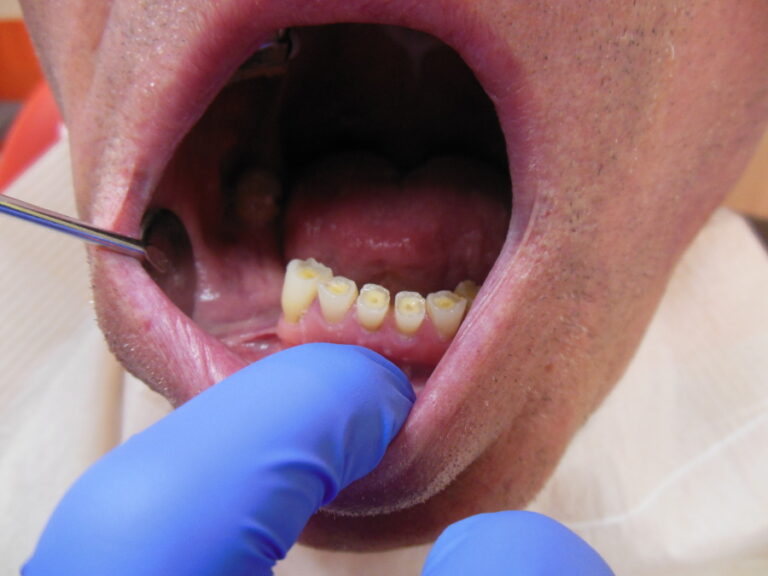

Przykłady implantologii

Zastosowanie implantoprotetyki w przypadku gdy klasyczna protetyka nie sprawdza się.